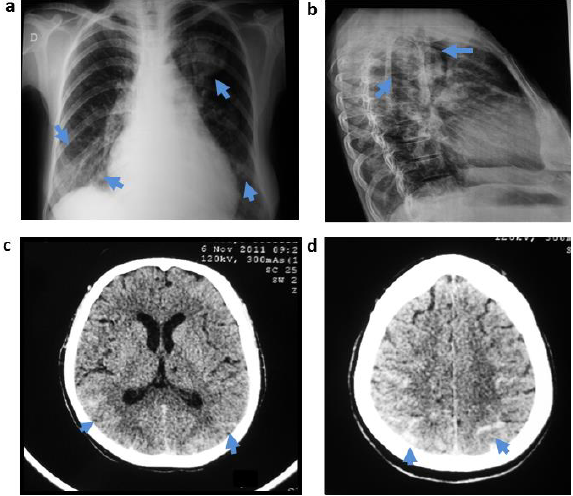

En la radiografía de tórax, en proyección postero-anterior y lateral, se observaron múltiples imágenes radio densas, homogéneas, redondeadas, de contornos bien definidos, distribuidas en ambos campos pulmonares, la de mayor tamaño ubicada en tercio superior de hemitórax izquierdo. Además, prominencia del tronco de la arteria pulmonar izquierda y cardiomegalia (figuras 1a y 1b).

La tomografía axial de cráneo sin contraste (figuras 1c y 1d), demostró la presencia de HSA tipo Fisher grado II a nivel de lóbulos occipitales y parietales. En la Arteriografía cerebral con sustracción digital en carótida externa izquierda, se observó FAV dural distal occipital izquierda con múltiples aferentes hacia seno transverso homo lateral con buen drenaje venoso anterógrado.